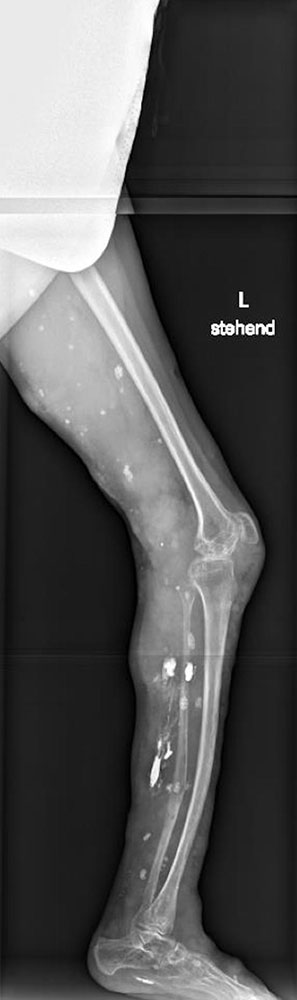

Störungen des Bewegungsapparates

Ausgedehnte intramuskuläre VM an den unteren Extremitäten und am Stamm können über eine asymmetrische Körperhaltung zu Fehlstellungen und Muskelschwäche mit erheblicher Einschränkung der Gehfähigkeit führen. Durch unsachgemäße oder zu radikale Therapiemaßnahmen kann es ebenfalls zu Langzeitstörungen der Mobilität kommen.

Bei Gelenk- und Knochenbeteiligung resultiert zudem eine erhöhte Frakturgefahr der oft begleitend dysplastischen Knochen, wobei dann die Bruchheilung erheblich verzögert erfolgt und es sogar zur Defektheilung kommen kann.

Die genannten Schäden am Bewegungsapparat sind dann ausgeprägter, wenn zusätzlich ein segmentaler Über- oder Unterwuchs vorliegt. Frühzeitig sollte dann ein Orthopäde, der über eine entsprechende Expertise verfügt, in die Betreuung eingebunden werden.